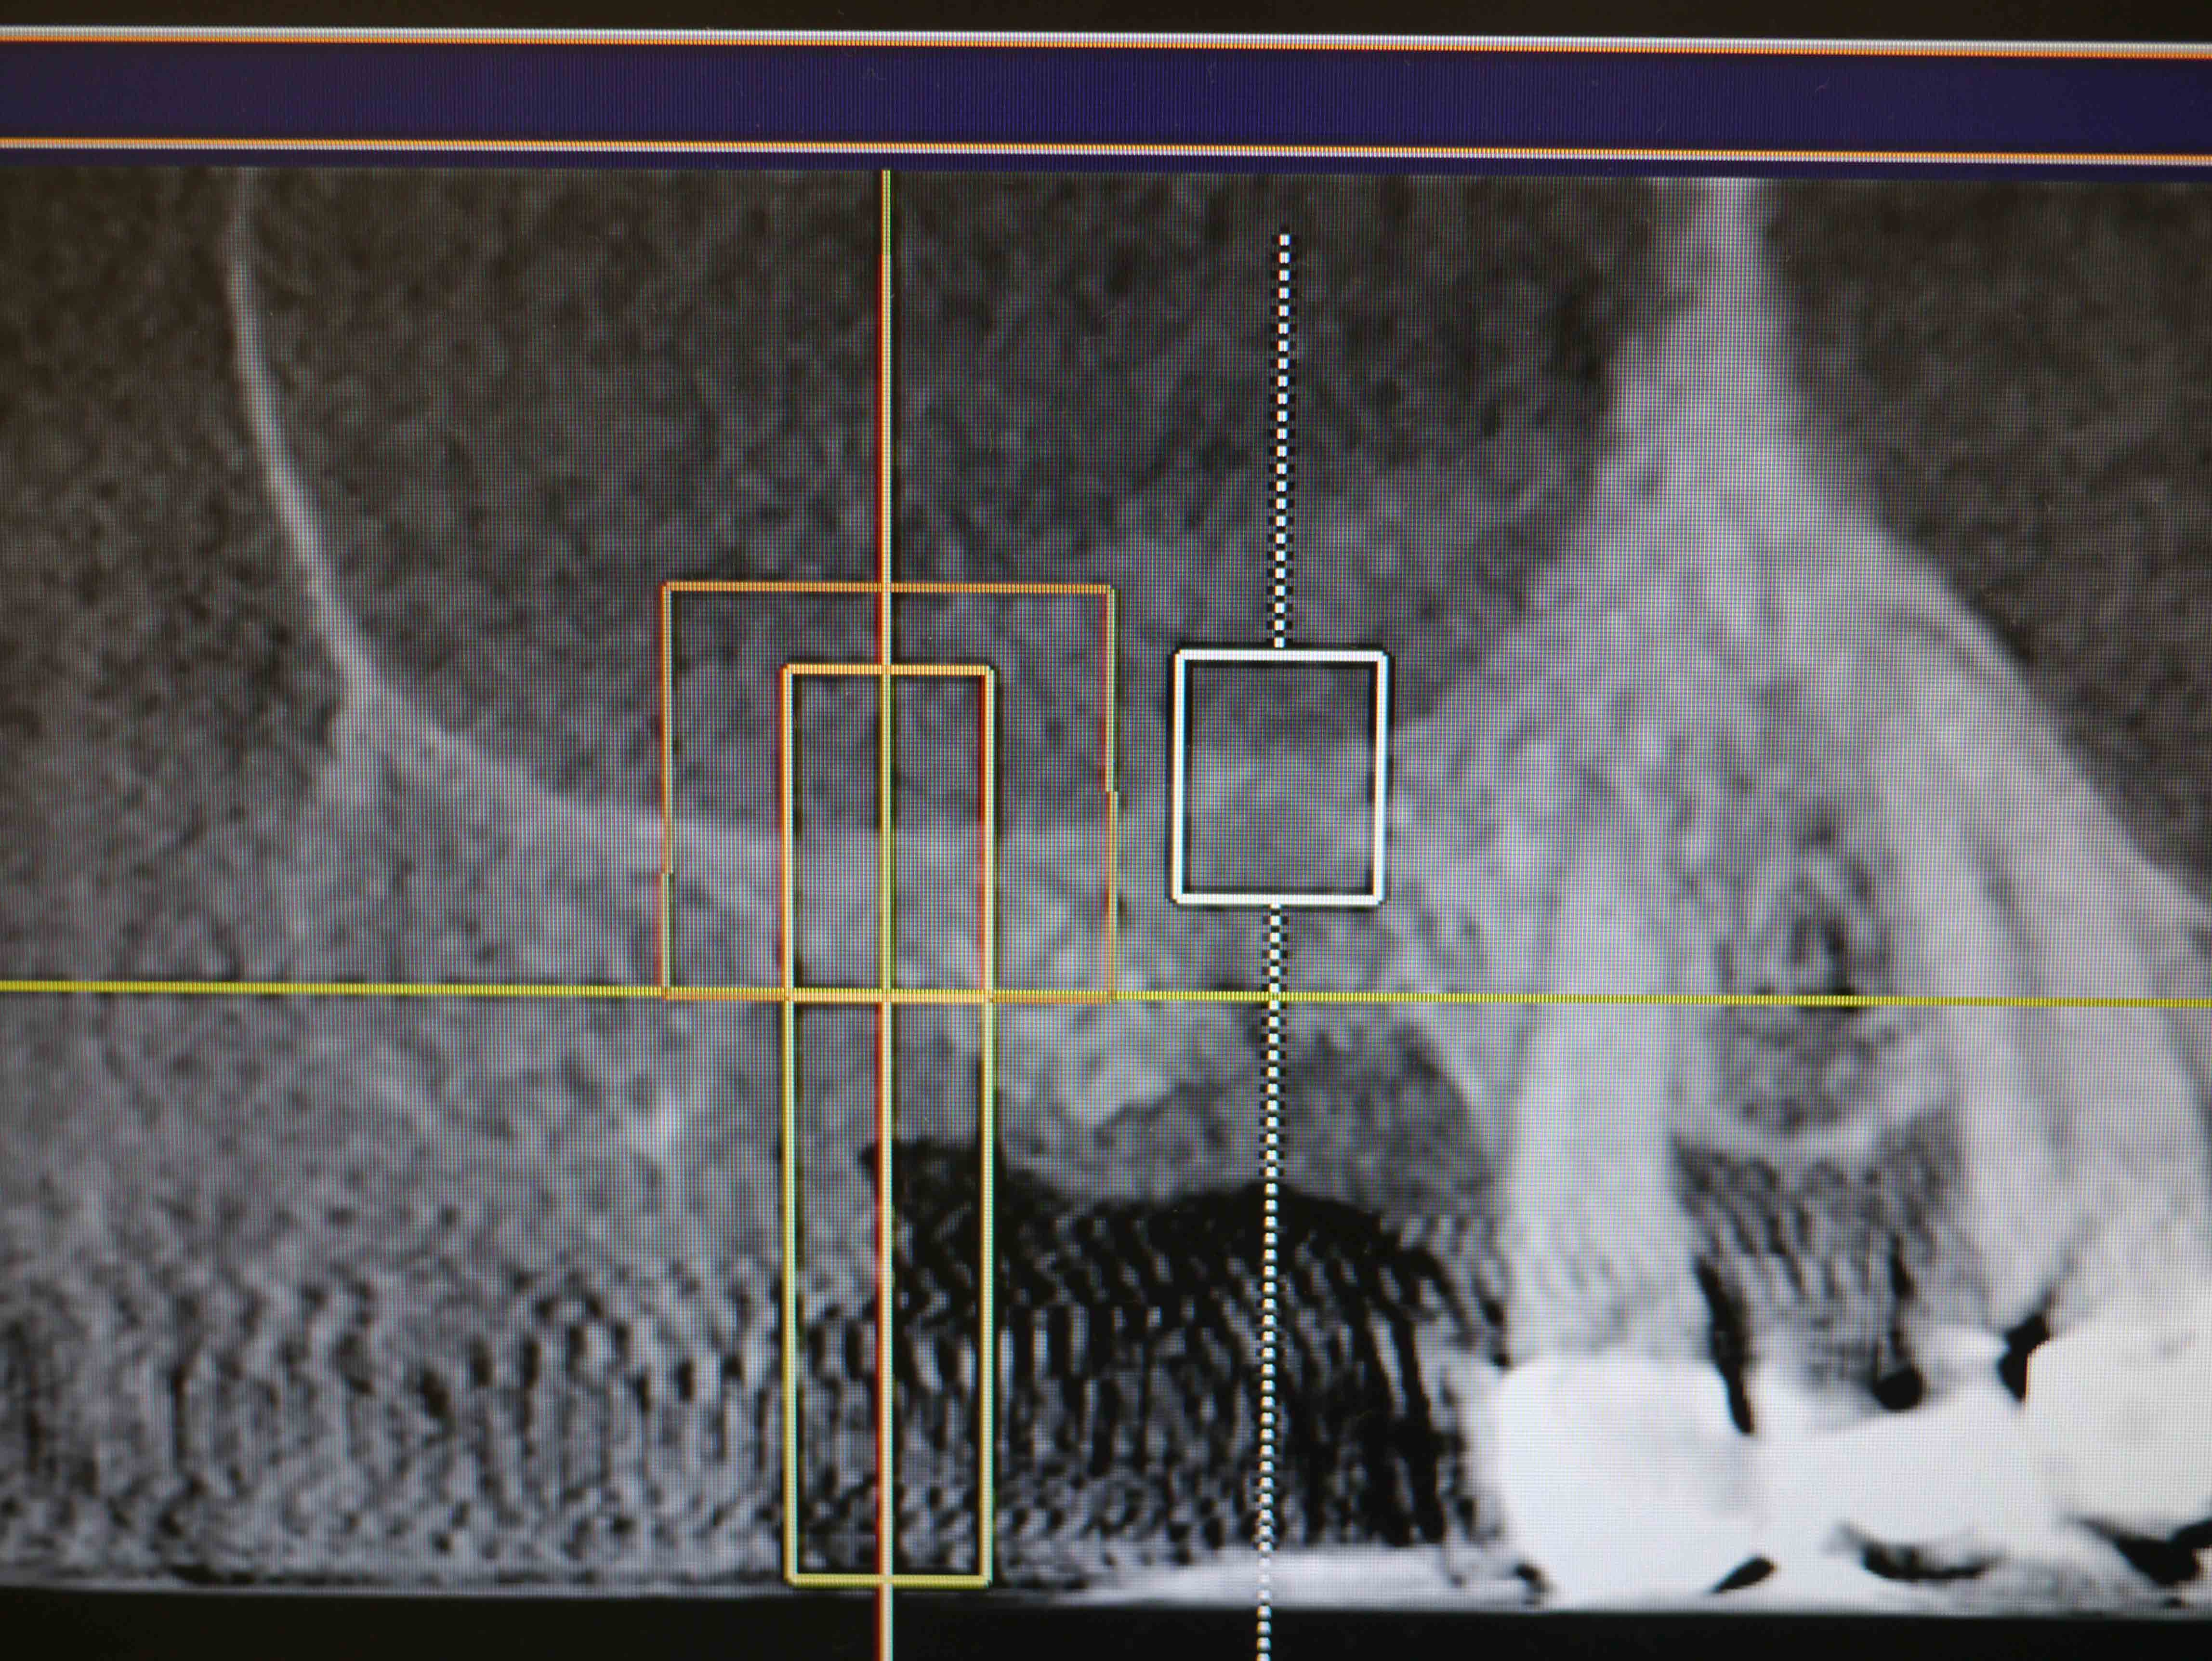

CT画像1

平成24年9月 手術前のCT画像

上顎洞底の骨の厚さが右上7番で最低4mm、6番で2mm程度

埋入予定の骨を側面(頬側)から見たCT画像